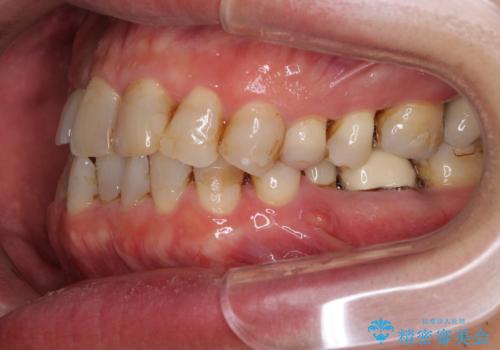

- 前歯のデコボコや、奥歯を咬んだときに痛みがあるとのことで来院された患者様です。

全体的に問題が多く、全てをしっかりと治療したいとのことでした。

全体的に中等度の歯周病と診断されたため、歯周外科処置やインプラントによる咬合回復から進めて行き、矯正治療による歯列改善を行った後にオールセラミッククラウンにて補綴することとしました。

矯正治療を希望して来院されましたが、歯周病を併発していたため、矯正治療開始前の処置が非常に多くなりました。特に歯槽骨の再生治療を行ったため、外科処置後の静置期間が長くなり、4年弱の治療期間となりました。